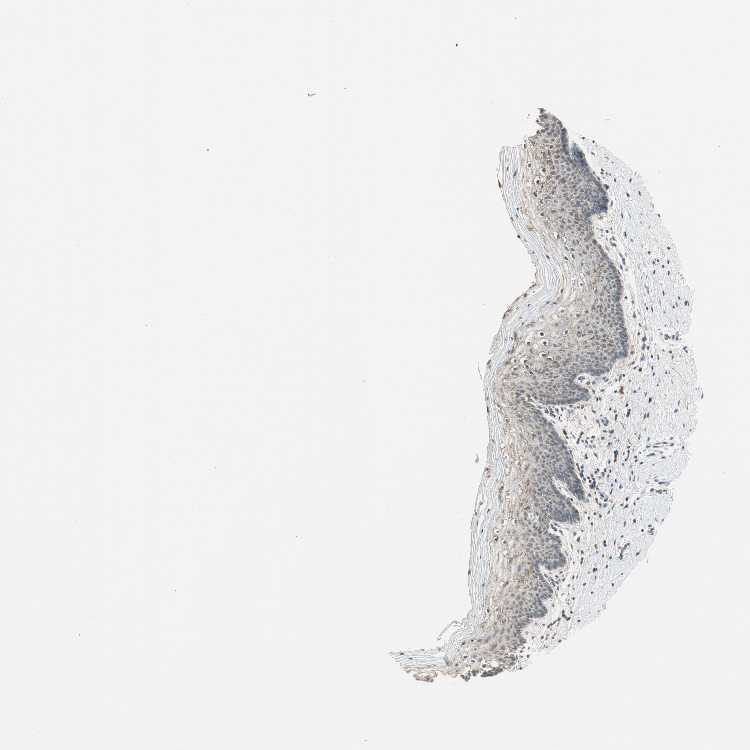

TISSUE PRIMARY DATA VAGINA Show tissue menu

VAGINA - Antibody stainingi

Antibody staining in the annotated cell types in the current human tissue is reported as not detected, low, medium, or high, based on conventional immunohistochemistry profiling in selected tissues. This score is based on the combination of the staining intensity and fraction of stained cells.

Each image is clickable and will lead to virtual microscopy that enables deeper exploration of all samples and also displays staining intensity scores, fraction scores and subcellular localization as well as patient and tissue information for each sample.

Antibody HPA005701

Squamous epithelial cells Low